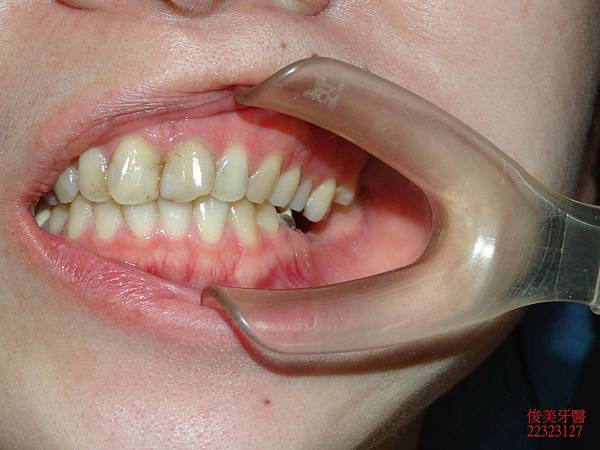

前面狀況。

牙齒排列不整。

牙縫蛀牙。

側邊咬合。

上排牙齒已有延長的現象,牙縫更容易塞東西,且沒有咀嚼功能。